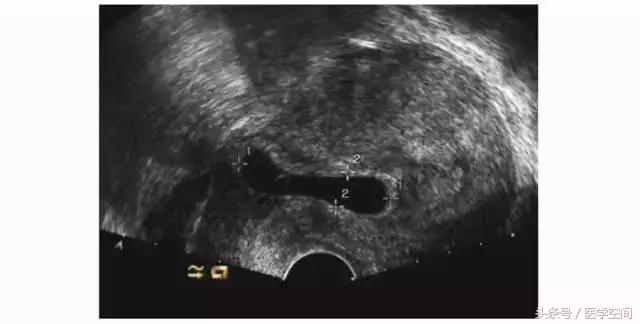

CSP超声漏诊进行了药流或人工流产、CSP自发流产不干净的患者,行超声检查时常表现为子宫剖宫产切口瘢痕处的不均质低回声肿块,CDFI在肿块周边常可探及丰富的血流信号(见图5),脉冲多普勒超声检查可探及低阻滋养动脉血流频谱,经验不足者可能会误诊为滋养细胞肿瘤,继而施以化疗。

图5不典型CSP的超声表现